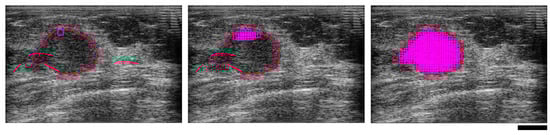

2.2. Ultrasound Data Analysis